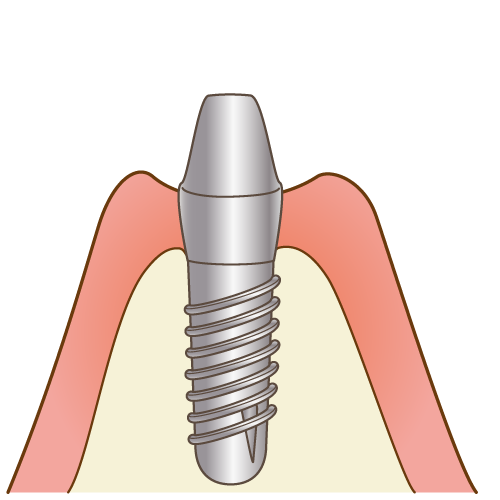

6二次手術

人工歯根の頭の部分を露出させ、ヒーリングアバットメント(連結部)を取り付け、歯肉の治癒を待ちます。

人工歯根の頭の部分を露出させ、ヒーリングアバットメント(連結部)を取り付け、歯肉の治癒を待ちます。

その後、1~4週間ほどで歯肉の状態を確認しながら、仮歯を作成し、清掃性や咬み合わせの模索をしっかりとしたのち、最終的な被せ物へと移行していきます。